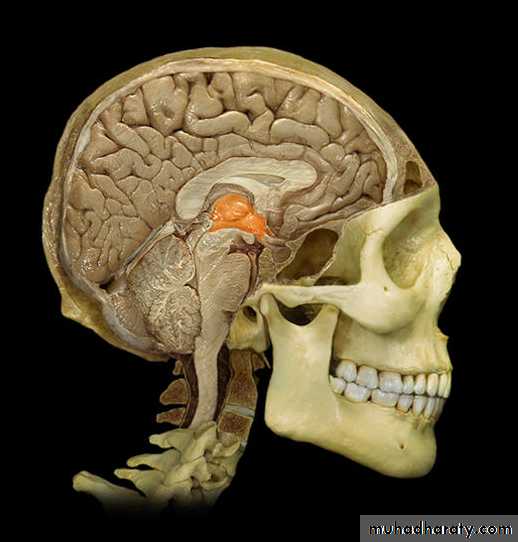

The Choroid Plexus

Choroid Plexus

• Choroid plexushang from the

roof of each

ventricle

• These plexuses

• form CSF

• The plexuses are

• clusters of thin

• walled capillaries

• enclosed by a

• layer of

ependymal cells

3rd Ventricle

• It lies below the lateral ventricles.

• It is a cavity of the diencephalon. In the roof there is

choroid plexus, that produce CSF.

4th Ventricle

It is a cavity of the rhombencephalon• It has a roof and floor.

• The floor is formed by two parts, medullary & pontine part.

• The roof formed by cerebellum

• It has 3 foramina, one is median (foramen of Magendie) located posteriorly and two are lateral (foramina of Lushka)